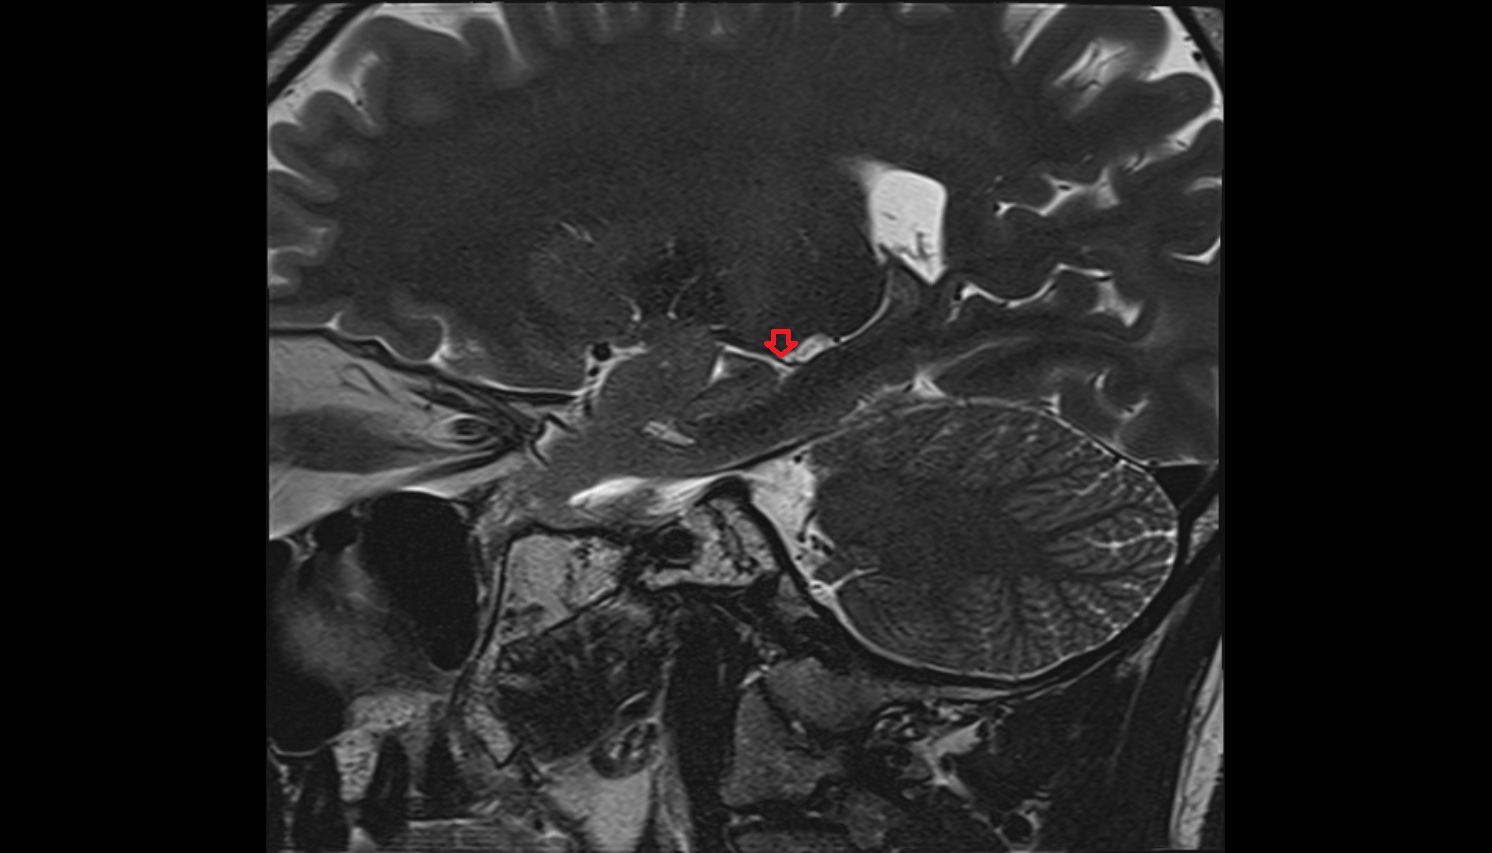

- Temporomandibular joint

- Articular disc of temporomandibular joint

- Mandibular condyle

- Mandibular fossa

- Articular eminence